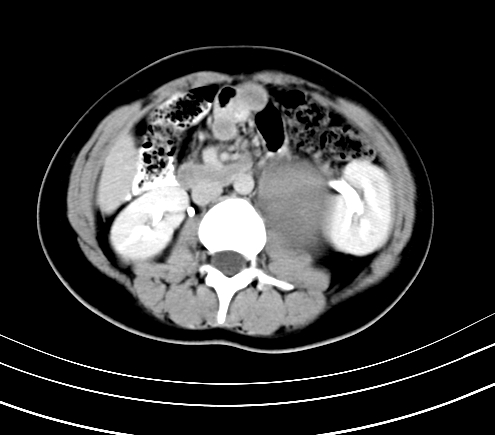

腹部平扫

动脉期

静脉期

延时5分钟

延时10分钟